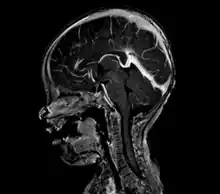

| Large arteriovenous malformation of the parietal lobe | |

A cerebral AVM diagnosis is established by neuroimaging studies after a complete neurological and physical examination.[5][13] Three main techniques are used to visualize the brain and search for an AVM: computed tomography (CT), magnetic resonance imaging (MRI), and cerebral angiography.[13] A CT scan of the head is usually performed first when the subject is symptomatic. It can suggest the approximate site of the bleed.[3] MRI is more sensitive than CT in the diagnosis, and provides better information about the exact location of the malformation.[13] More detailed pictures of the tangle of blood vessels that compose an AVM can be obtained by using radioactive agents injected into the blood stream. If a CT is used in conjunction with an angiogram, this is called a computerized tomography angiogram; while, if MRI is used it is called magnetic resonance angiogram.[3][13] The best images of a cerebral AVM are obtained through cerebral angiography. This procedure involves using a catheter, threaded through an artery up to the head, to deliver a contrast agent into the AVM. As the contrast agent flows through the AVM structure, a sequence of X-ray images are obtained.[13]